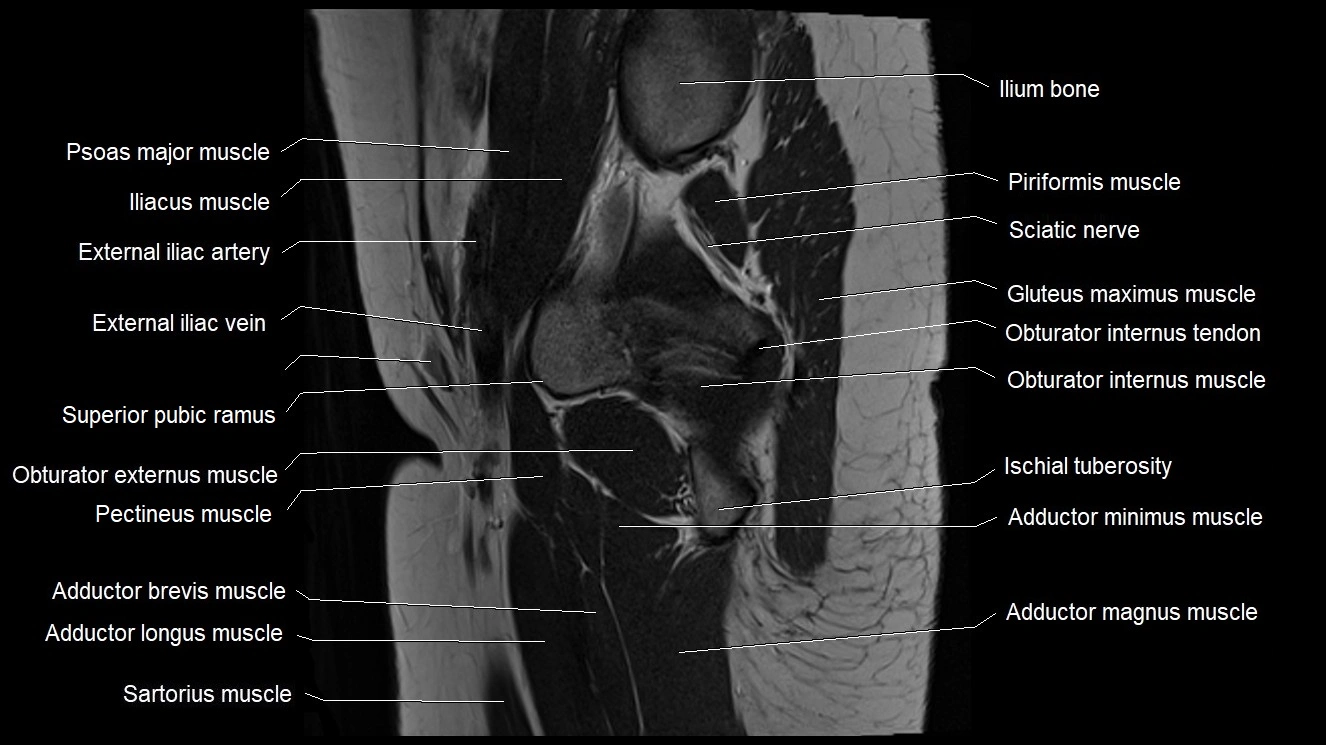

- External iliac artery

- External iliac vein

- Gluteus maximus muscle

- Ilium bone

- Inferior gemellus muscle

- Ischial tuberosity

- Lumbosacral trunk

- Obturator internus muscle

- Obturator internus tendon

- Pectineus muscle

- Psoas major muscle

- Superior pubic ramus